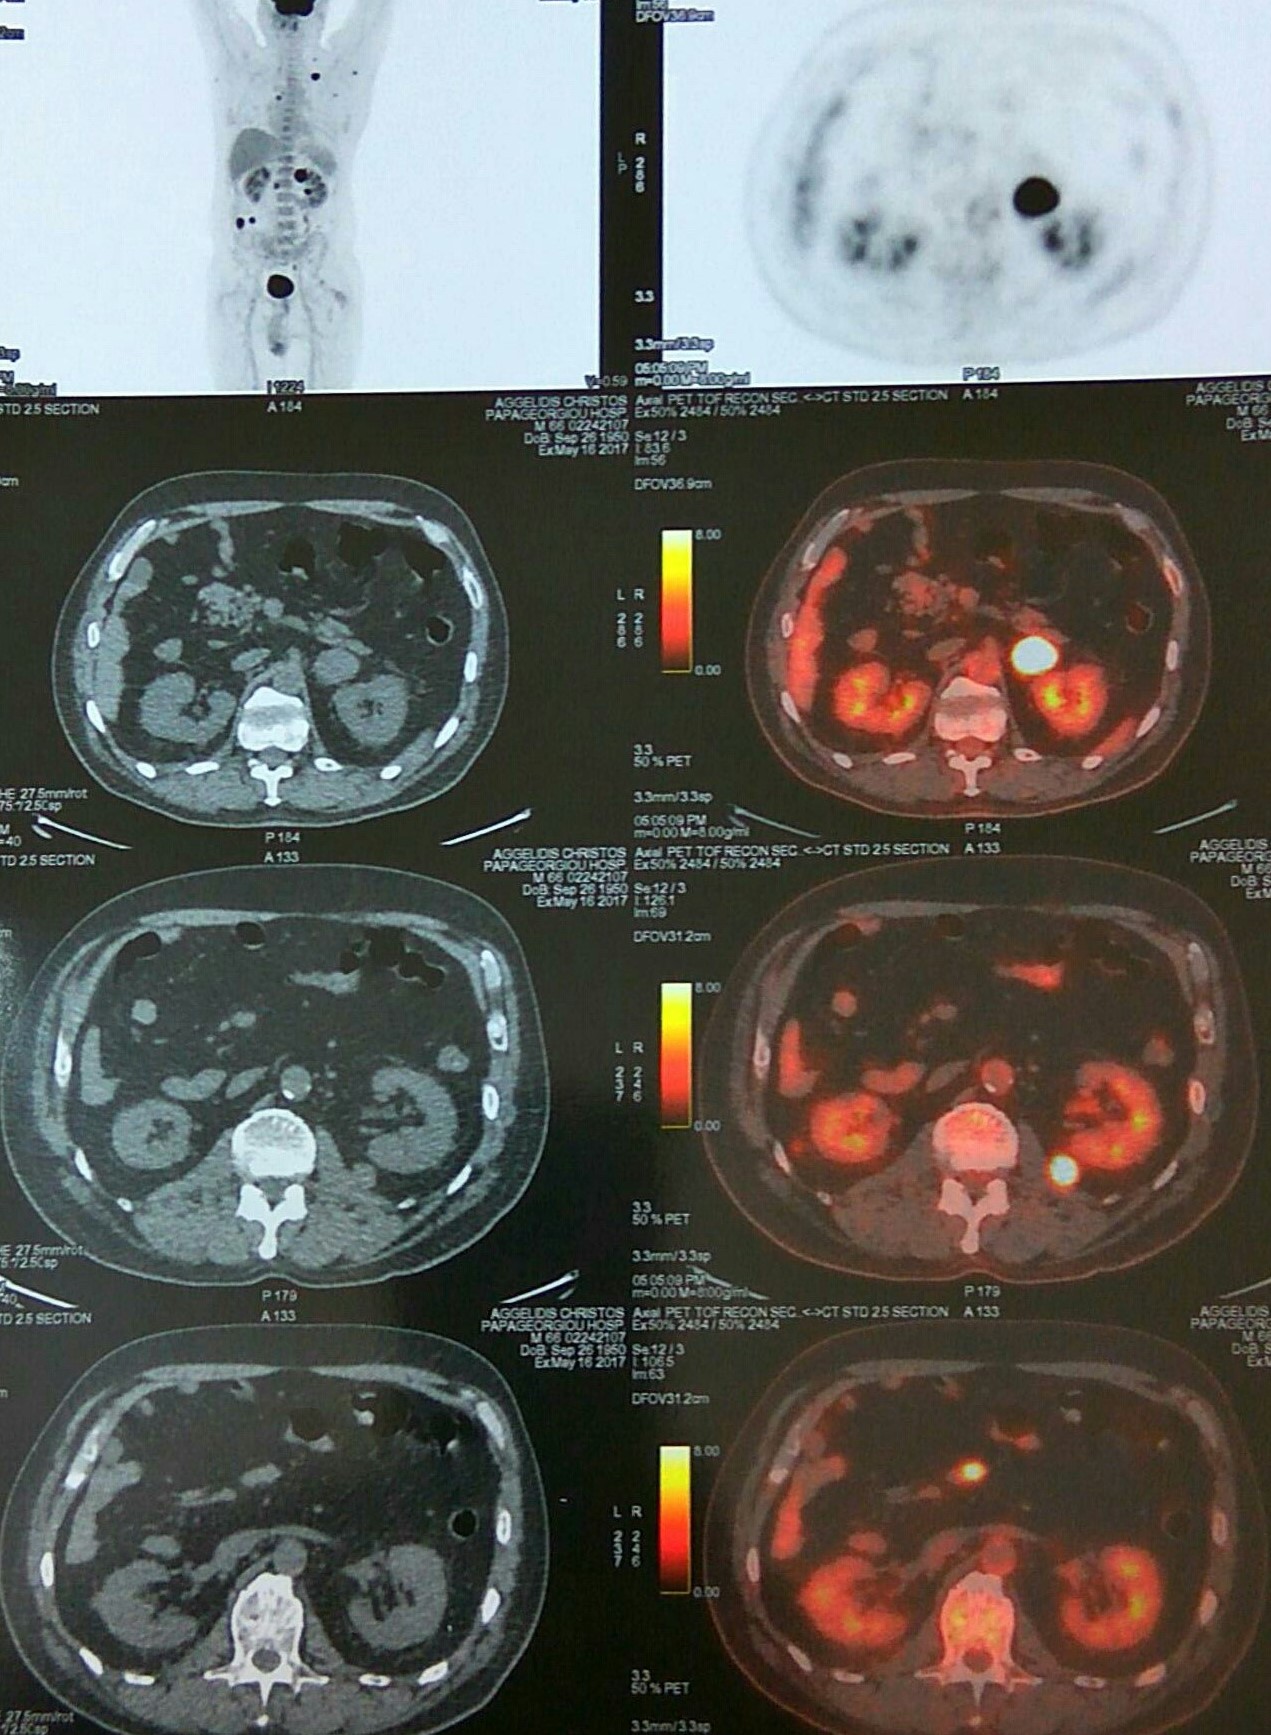

Αξονική τομογραφία κοιλίας. Φεβρουάριος 2017. Εμφανίζεται η υποτροπή του οπισθοπεριτοναϊκού αγγειοσαρκώματος (κόκκινα βέλη)